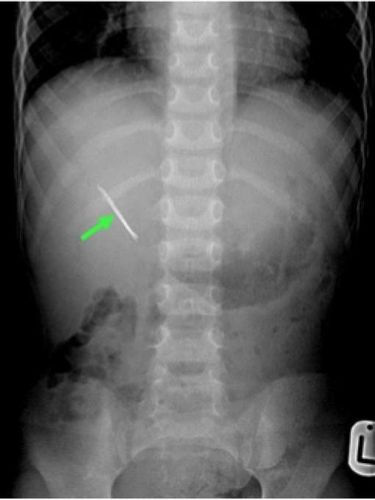

Karena tidak kunjung sembuh meski sudah mengonsumsi antibiotik, si bocah sempat dibawa ke sebuah rumah sakit. Pemindaian sinar X menunjukkan ada jepit rambut di perut bagian kanan atas. Barulah pada saat itu, si bocah mengaku pernah tak sengaja menelan jepit rambut sebulan sebelum gejalanya muncul.

Namun pada saat itu, dokter masih yakin jepit rambut akan keluar dengan sendirinya melalui saluran cerna. Januari 2015, si bocah dibawa ke rumah sakit lain tempat Yousef bekerja. Pemeriksaan dengan CT Scan menunjukkan bahwa jepit rambut tidak berada di saluran cerna, melainkan terjebak di ginjal kanan.